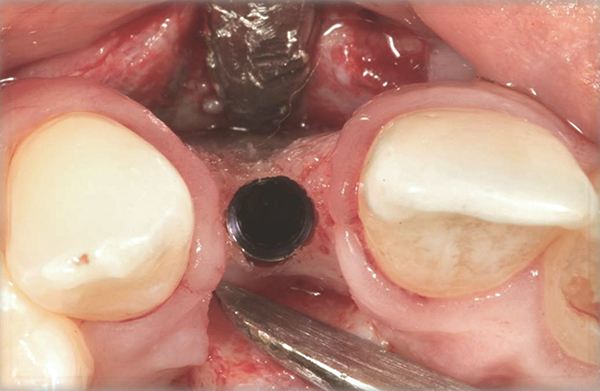

Fig 21. A dental implant was placed at the site of tooth No. 10. A defective buccal ridge was noted.

Figure 21

Fig 22. A straight healing abutment was attached to the implant. The barrier (held back with the periosteal elevator) was placed before the bone graft insertion.

Figure 22